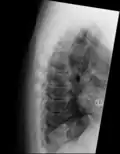

Confluent ossification of multiple contiguous vertebral bodies in diffuse idiopathic skeletal hyperostosis (DISH) -

"Melted candle wax" appearance of calcification and ossification in diffuse idiopathic skeletal hyperostosis (DISH). Note the preponderance on the patient's left side (right side of image). -